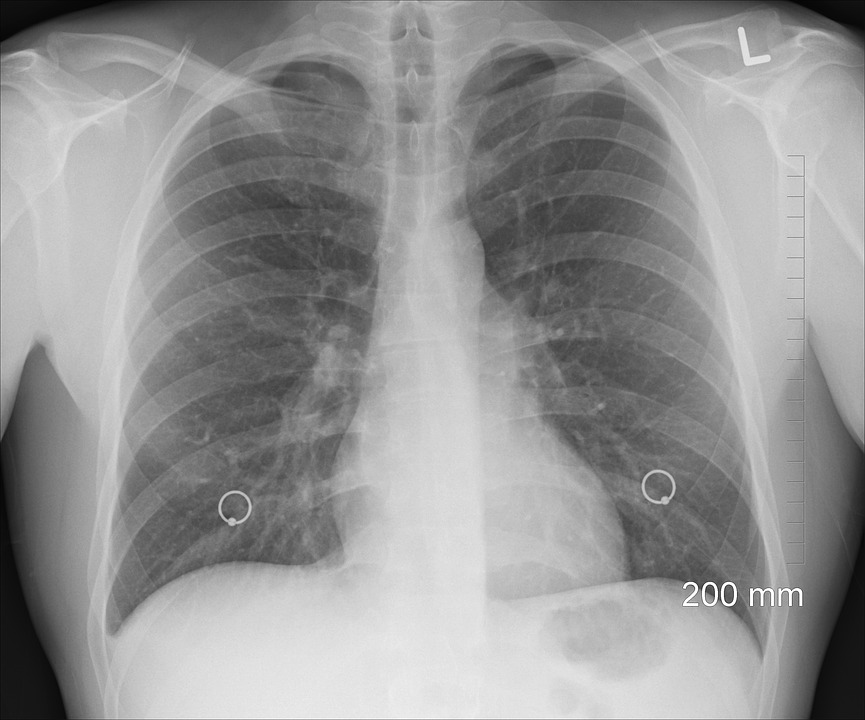

Se zmíněnými druhy plicní hypertenze se v Česku léčí přibližně 1000 pacientů, každý rok jich přibližně 150 přibude. Foto: Pixabay